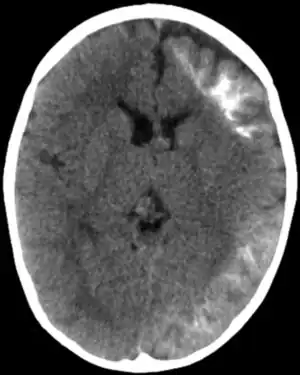

| CT scan of Sturge-Weber syndrome | |

The underlying cause is most often an error in the GNAQ gene, in some cells.[2] It generally occurs randomly rather than being inherited from a person's parents.[2] This results in some blood vessels not forming properly.[2] Diagnosis is often based on symptom and medical imaging.[4] A CT or MRI may show tram track calcifications and pial angiomatosis.[1] It is a type of phakomatoses.[1]

CT and MRI are most often used to identify intracranial abnormalities. When a child is born with a facial cutaneous vascular malformation covering a portion of the upper or the lower eyelids, imaging should be performed to screen for intracranial leptomeningeal angiomatosis. The haemangioma present on the surface of the brain is in the vast majority of cases on the same side as the birth mark and gradually results in calcification of the underlying brain and atrophy of the affected region.[9]